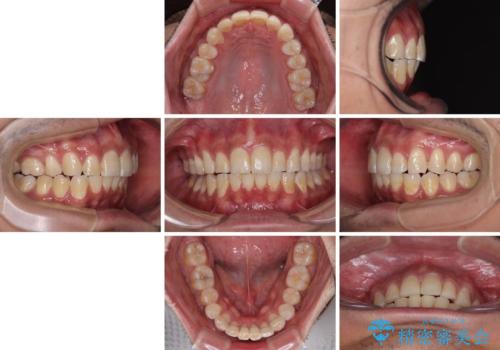

- 深い咬み合わせと前歯のデコボコを改善したいとのことで来院された患者様です。

口元の突出感はないものの、上顎前歯のデコボコが著しく、右側の咬み合わせがずれていたため、上顎右側第一小臼歯1本を抜歯することとしました。

咬合力が非常に強く、抜歯したスペースがなかなか閉じないであろうことは予想できましたが、思っていた以上に期間がかかりました。

前歯のすり減りも著しかったため、仕上げの位置の調整にも期間を要しました。